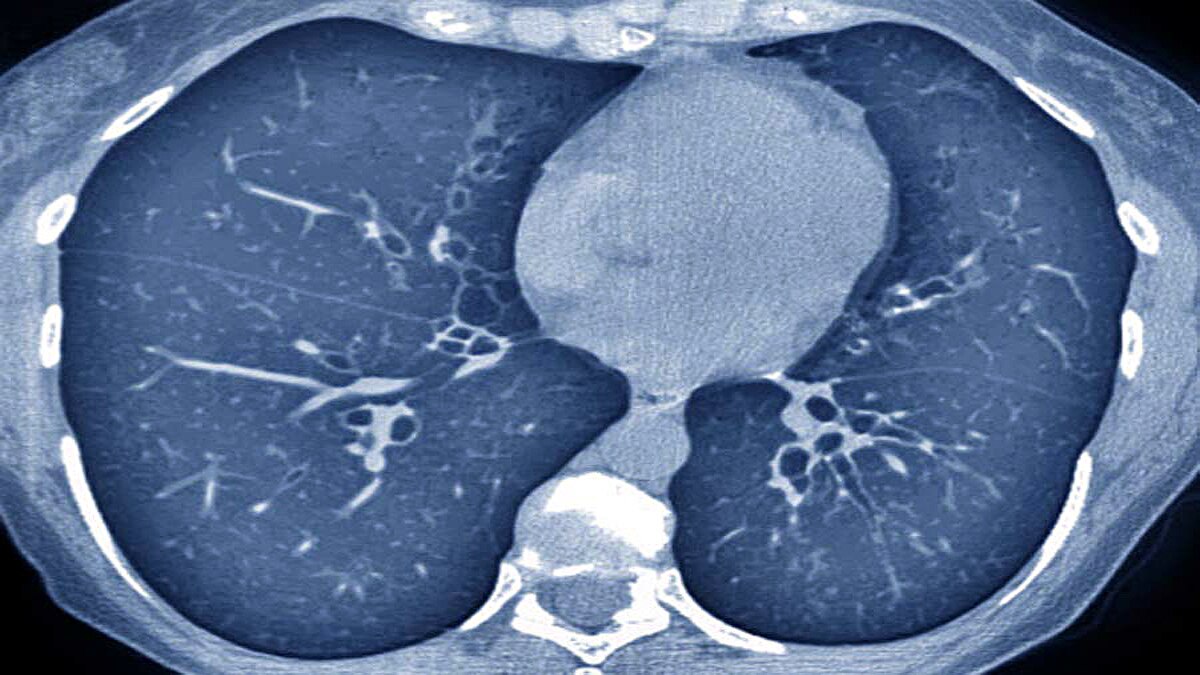

डॉ. उदवादिया ने बताया कि कुछ मरीजों को ठीक होने के बाद भी उनके घर पर भी ऑक्सीजन की जरूरत पड़ रही है. मरीज के ठीक होने के तीन महीने बाद जब सीटी स्कैन किया जाता है तो उनके फेफड़ों की स्थिति बहुत खराब मिलती है. तीन दशक पहले लंग फाइब्रोसिस (Lung Fibrosis) बीमारी आमतौर पर बहुत कम लोगों को होती थी. ज्यादातर बुजुर्गों को होती थी. (फोटोः गेटी)